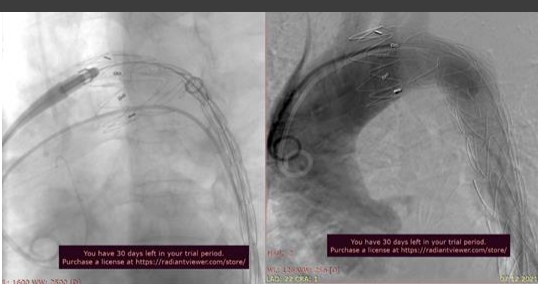

After spinal anesthesia, placement of a central catheter into the jugular vein on the right, and preparation of the surgical field of the upper third of the left thigh in the groin area, a skin and subcutaneous fat incision was made in the projection of the common femoral arteries. After opening the femoral fascia, blunt and sharp access was made to the common femoral artery (BOA) on the left. Then a standard thoracic aortography was performed, which revealed an aneurysm of the descending thoracic aorta. (Fig.2.)

Figure 2. Aneurysm of the descending thoracic aortaThe stent-graft was removed by 1/4 of the length of the delivery catheter, in the projection of the landing zone at the orifices of the internal carotid artery (ICA) and the left subclavian artery (LAS), the proximal end of the stent-graft was fenestrated in the form of a wedge "on the table". Next, the selected CFA is pierced on the left. On a diagnostic catheter, a superrigid guidewire was introduced into the aortic arch and its distal end was placed in the ascending aorta. The catheter was removed and a partial arteriotomy was performed. After expanding the vascular access through a superrigid guidewire, a modified thoracic stent-graft Valiant Thoracic StentGraft 36.0x36x200.0 mm (No.……series…production….) was delivered to the aortic arch, mounted on a Captivia delivery system (company?).

Figure.3. Angiography for stent graft sizing

Then, under the control of angiography (Fig. 3.) and fluoroscopy, the stent-graft was placed in the descending thoracic aorta, capturing the area of the dissecting aortic defect, proximal to the celiac trunk. After the stent-graft was exposed, the “crown” of the proximal apparatus was opened immediately after the brachiocephalic trunk originated so that the fenestrated zone was at the border of the origin of the left common carotid artery and the orifice of the left subclavian artery. (Fig. 4.) During intermediate angiography, the crown of the stent graft was fully opened, the arteries of the aortic arch were patent.

Figure 4. Fenestration of the zone where the left common carotid artery and the mouth of the left subclavian artery will be locate

Figure 5. Stent graft fully deployed and implanted

The stent graft is fully deployed and implanted (at what pressure and for how many seconds, once or repeatedly?) (Fig. 5.) The delivery system is removed. During the control aortography, the stent graft and arteries of the aortic arch were completely patent, the false lumen was not contrasted. The CFA defect on the left was sutured with interrupted vascular sutures with a 6/0 Prolene suture. Hemostasis achieved. The wound was sutured in layers, drainage was installed, and an aseptic dressing was applied. The CFA introducer is on the right, the puncture site is removed, closed with the Angioseal 6F apparatus, an aseptic dressing is applied.